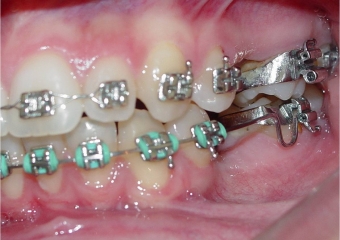

Imagem inicial